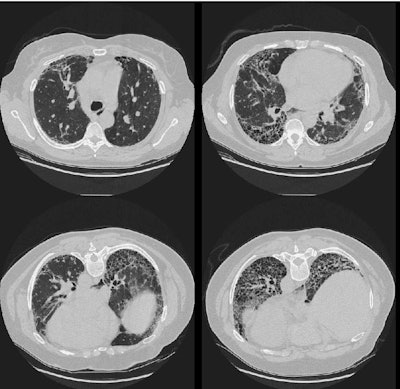

The CT scan (supine and prone images) reveal extensive interstitial fibrosis with honeycombing.